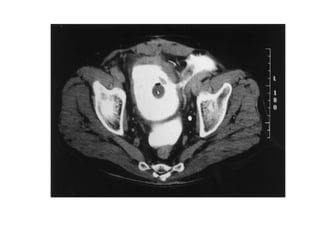

The kidneys can be injured by blunt or penetrating trauma, requiring timely medical evaluation. The kidneys are normally protected by back muscles but can be damaged by severe impacts or objects piercing the skin. Blunt trauma may cause bruising while penetrating injuries like gunshots can enter elsewhere and travel to the kidneys. Most kidney injuries are minor but evaluation with imaging tests like ultrasound or CT scans helps classify the injury and guide management, which may include rest, antibiotics, surgery, or nephrectomy in more severe cases.